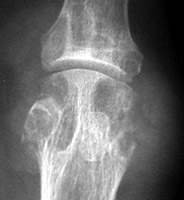

Reiter's: Erosion and productive changes 1st MTP joint.

++